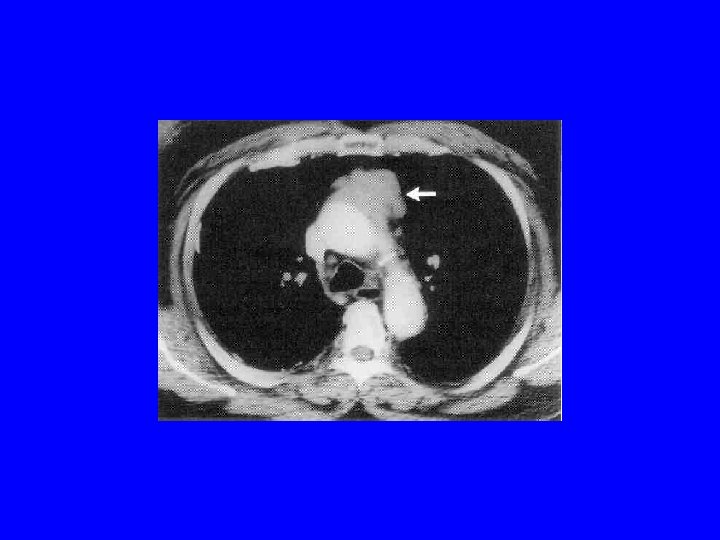

MG: diagnostyka • Test z tensilonem • badania elektrofizjologiczne: elektrostymulacyjna próba męczliwości, elektromiografia pojedynczego włókna mięśniowego (SFEMG) • przeciwciała przeciwko ACh. R, Mu. SK • TK śródpiersia

ZESPÓŁ LAMBERTA-EATONA • w 60% współistnieje rak drobnokomórkowy płuc (O’Neil 1988), białaczki, chłoniaki, rak prostaty, ale również grasiczak!!! • LEMS może wyprzedzać kliniczne objawy choroby nowotworowej